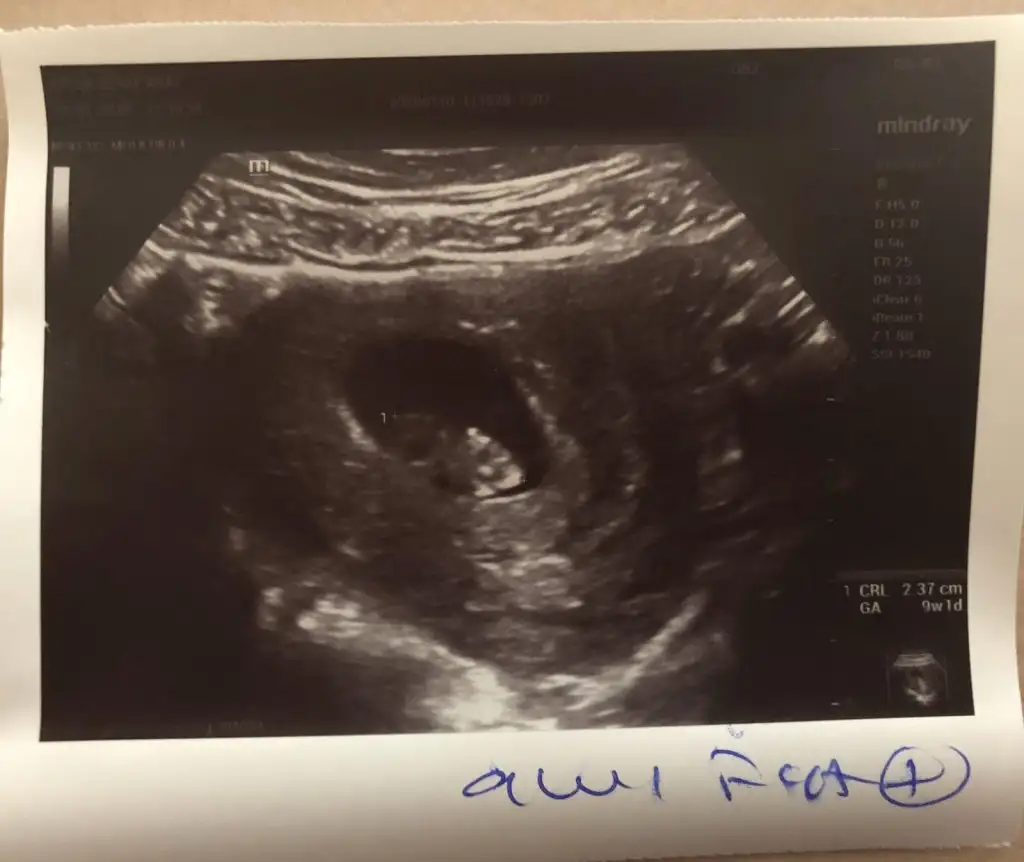

• Screenshot_20200104_122635_com.huawei.himovie.overseas.webp

Screenshot_20200104_122635_com.huawei.himovie.overseas.webp

13,7 KB · Görüntüleme: 64